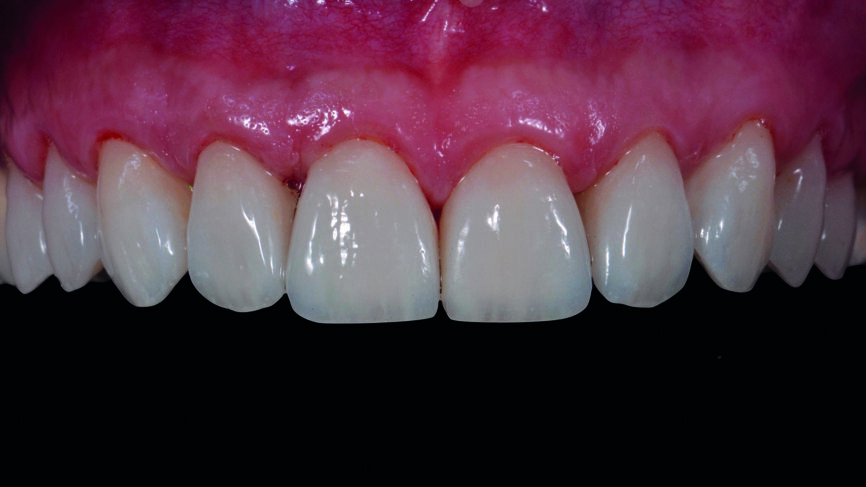

Fig. 17a : Résultat final une semaine plus tard.

Fig. 17b : Résultat final une semaine plus tard, vue de face

Le clinicien et la patiente ont décidé subjectivement un scellement des facettes en céramique feldspathique en raison des légères différences dans la longueur des incisives centrales des deux jeux. Les procédures adhésives ont suivi (Figs. 16a–f) et des photographies intra-orales et extraorales ont finalement été prises une semaine plus tard (Figs. 17a–e).

La prise d‘une empreinte intra-orale numérique est une autre procédure clinique qui s‘avère excellente par rapport à la technique d‘empreinte classique. Le plan de traitement numérique et le mock-up associé sont de puissants outils de communication à la disposition du chirurgien-dentiste, quoique l‘utilisation du logiciel exige des compétences particulières. Au regard du travail en laboratoire, mis à part les étapes de coloration et de glaçage, la plupart des techniques analogiques demandent plus de temps (fabrication des modèles positifs unitaires réfractaires, fabrication des facettes, ajustements) (Figs. 18a et b). Dans ce cas, le résultat esthétique des facettes en céramique feldspathique résultait d‘un choix subjectif mais le flux de travail analogique est beaucoup plus exigeant. Vu la réduction de la difficulté, de la vitesse, de la complexité et du désagrément causé au patient, l‘approche numérique est plutôt à privilégier (Figs. 18a et b).